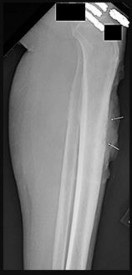

Figures 9a through 9d are the anteroposterior and lateral radiographs, CT scan, and technetium bone scan of a 12-year-old boy who has experienced 7 months of pain in his lower leg. The pain limits his ability to participate in sports and he is having difficulty sleeping. He is afebrile, and laboratory study findings including an erythrocyte sedimentation rate, C-reactive protein, and complete blood count are within normal limits.

The images and clinical history support a diagnosis of osteoid osteoma, which most commonly occurs in adolescence. Although these lesions can be seen in any bone, they are usually located in the femur and tibia. The significant inflammatory response to this tumor is secondary to high levels of prostaglandin production. Characteristic night pain is relieved with nonsteroidal anti-inflammatory drugs (NSAIDs) or by aspirin.

Radiographic images show thickened bone and a small central nidus. Thin-cut CT scan is the imaging of choice to visualize the nidus. A bone scan is associated with uptake but is not specific. Treatment options include expectant management with NSAIDs and observation under the premise that these lesions eventually burn out. Contemporary treatment involves RFA. Historically, these lesions were treated with en bloc resection; however, this technique has largely fallen out of favor because of the high efficacy and comparative low morbidity associated with RFA.

When an osteoid osteoma occurs in the spine, it is located in the posterior elements, and paraspinal pain and scoliosis often are present.